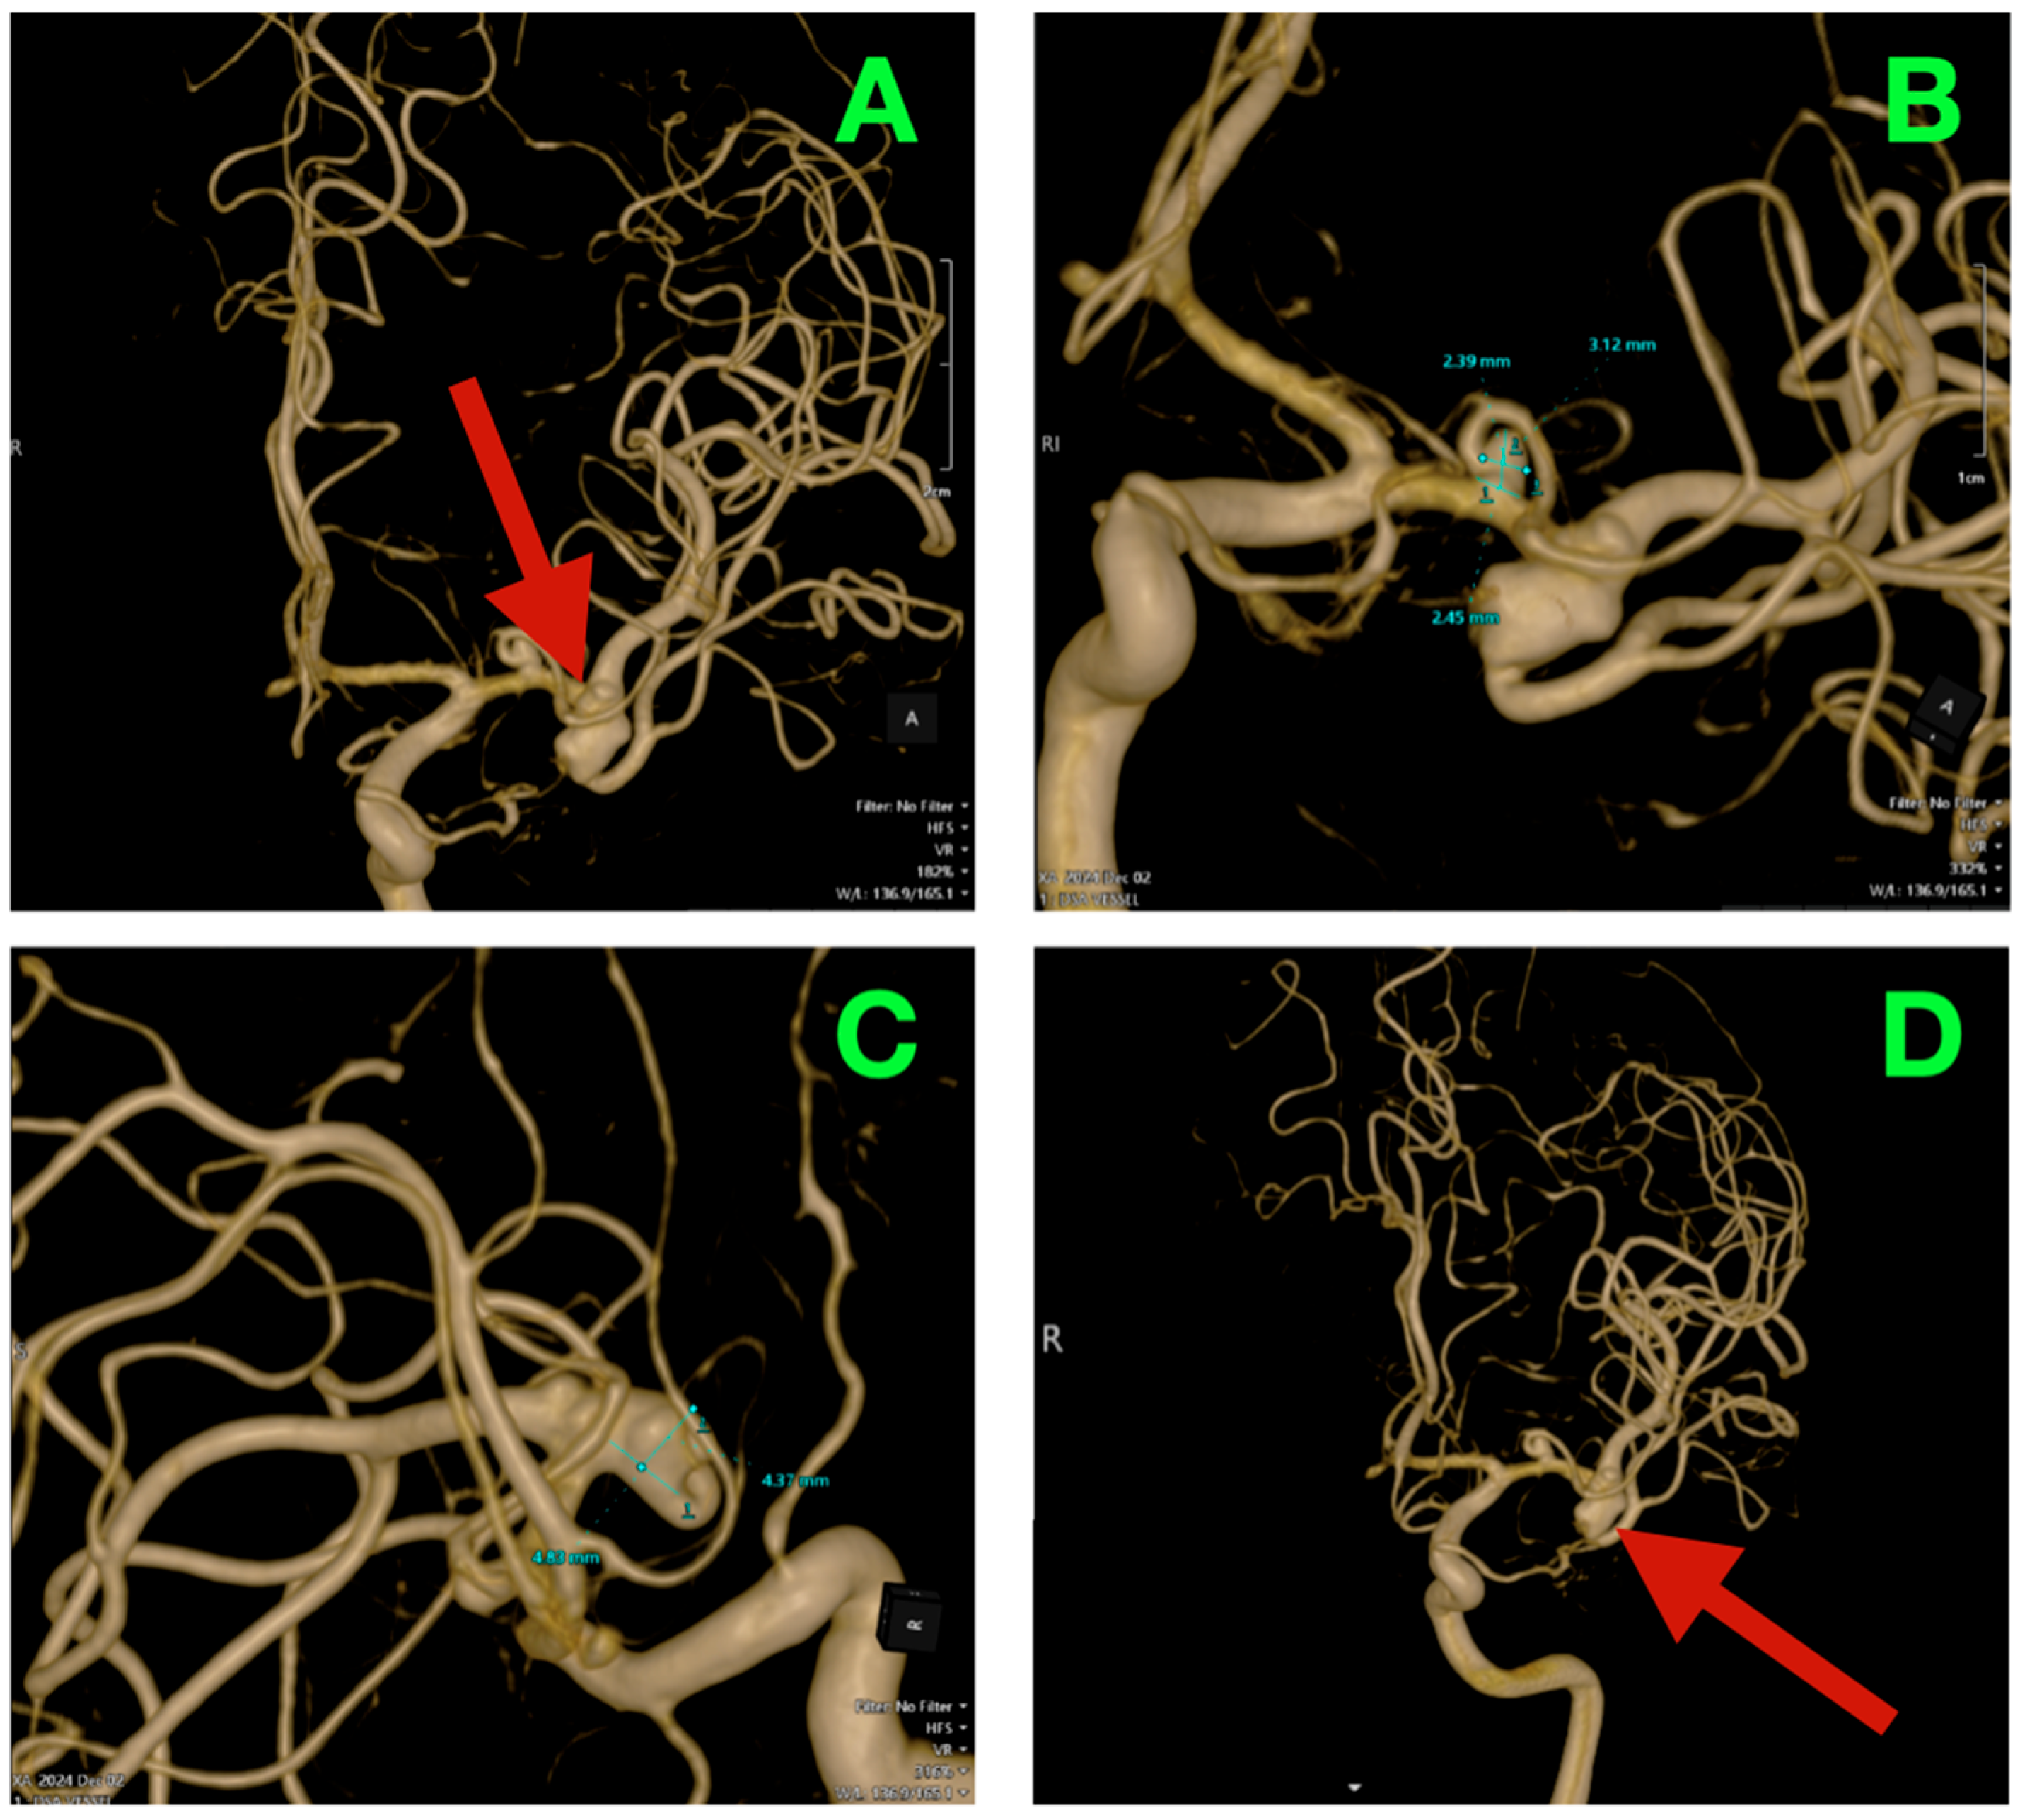

2.3. Three-Dimensional Rotational Angiography (3DRA) and CTA Reconstruction

High-resolution 3D rotational angiographic volumes were collected, and volumetric rendering and CTA were undertaken (Figure 2A–D). This reconstruction optimally adapted to isolate the traditional overlap of vessels or planar angiography and enabled surgical simulation. Additionally, it offered analysis of neck geometry, dome orientation, and angles of take-off of the branches in orthogonal planes, along with great detail to preoperative planning, discarding a virtual “clip trajectory” workable area. The anterosuperior projection of the bifurcation aneurysm was again confirmed, with the dome axis pointing toward the mid-insular cortex. The superior M2 trunk had a narrow angle of take-off at 54° from the superior neck border, while the inferior trunk originated in a more posterior and inferior orientation with a 68° angle that created an acute “tight fork”. This neck geometry significantly reduced tolerance for misalignment of the clip blade because even slight decreases in alignment can add a partial increase in compromise of the lumen—especially if the clip was aligned in a position that would yield a submillimeter misalignment. The neck contained 1.8 mm of orifice from the superior M2 and 1.4 mm of orifice from the inferior M2, as calculated on centerline flow reconstruction. The perforator anatomy of the M1 fusiform aneurysm was elaborated upon with remarkable fidelity. The lenticulostriate had explicitly dissipated perpendicularly on the dorsal wall with their immediate posterior vector direction of the perforated substance. The two biggest perforators measured 460 μm and 420 μm at their origins and were tapering quickly within 1.2 mm of take-off. This made both arteries very sensitive to even glass-like movement in the parent vessel from the clip applied to the bifurcation lesion. The inter-aneurysmal distance was short at 4.7 mm, which allowed for potential mechanical manipulation of the other vessel even if we only performed the dissection on one lesion.

Figure 2.

Three-dimensional rotational angiography and CTA volumetric reconstruction of the left MCA complex. (A) 3DRA, left internal carotid artery injection, anterolateral oblique projection. The bifurcation aneurysm arises at the M1 division point, with the broad neck partially incorporating both superior and inferior M2 origins. Note the anterosuperior dome projection toward the mid-insular cortex and the tight angular divergence of the M2 trunks (“tight fork” configuration), leaving minimal tolerance for clip blade malrotation. (B) 3DRA, orthogonal craniocaudal projection. The dome’s spatial relationship to the superficial Sylvian venous complex is evident, with the shortest opercular vein lying within 3 mm of the aneurysmal wall. The fusiform M1 dilation is visible proximally on the dorsal surface, directly within the lenticulostriate perforator belt. (C) CTA bone–vascular fusion, lateral projection. Depth mapping from the sphenoid ridge shows the bifurcation aneurysm positioned approximately 17 mm deep, corresponding to the mid-third Sylvian fissure corridor, while the fusiform aneurysm lies deeper (~23 mm), just proximal to the genu of the MCA. (D) CTA bone–vascular fusion, inferolateral projection. The lenticulostriate perforators arising from the fusiform M1 segment are visualized with submillimetric resolution, demonstrating perpendicular dorsal take-off toward the anterior perforated substance, underscoring the extreme vulnerability of these vessels to even minimal parent vessel displacement during bifurcation clip application.

Bone surface reconstruction suggested that the bifurcation aneurysm was situated approximately 17 mm deep to the sphenoid ridge, corresponding to the origin of the Sylvian fissure at or near the mid-third Sylvian fissure exposure, while the fusiform aneurysm was much deeper at 23 mm from this same cortical surface landmark, and just proximal to the genu of the MCA.